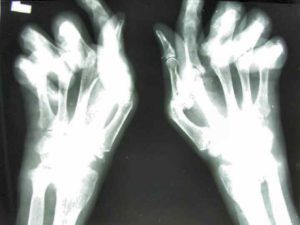

Патология суставов значительно ограничивает подвижность и приводит к невозвратным повреждениям суставов. Одно из распространенных детских заболеваний, которое приводит к поражению опорно-двигательного аппарата — ревматоидный артрит.

Ювенильный ревматоидный артрит протекает с деструкцией хрящевых структур на фоне воспалительных изменений. Встречается у детей до 16 лет, может сопровождаться поражением внутренних органов и различными клиническими проявлениями. Заболевание приводит к ослаблению организма, снижению иммунных функций и болезненности.

Главный клинический признак болезни — скованность суставов, отечность тканей над ними, болезненность и покраснение кожи. Для детей поражение суставов опасно тем, что может повлиять на зоны роста и нарушить физическое развитие ребенка.

- клинические: артрит, симметричное поражение структуры суставов, возникновение контрактур, воспаление околосуставных структур, скованность движений по утрам, атрофия мышечной ткани, поражение глаз, ревматоидные узелки на коже.

- рентгенологические критерии: перестройка костной ткани, остеопороз, сужение щели между суставами, нарушение зон роста, вовлечение в процесс шейных позвонков.